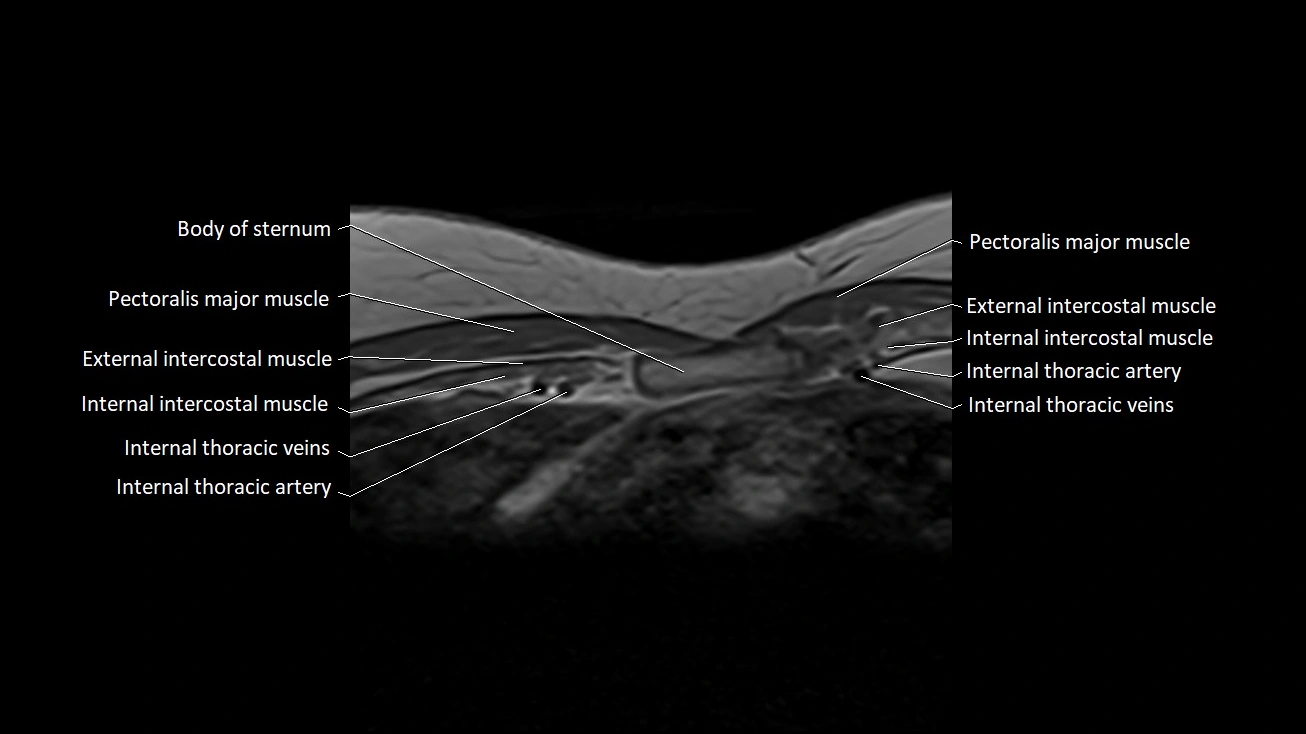

MRI images

image